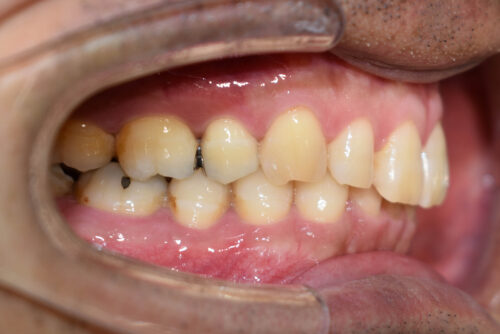

ワイヤー矯正治療12か月後です。

本症例も

左下の部分矯正治療をご希望でしたが、

スペースがなく 歯を抜かないと 並べられなくなってしまうため、

全顎矯正治療をおすすめして

開始しましたが、

非抜歯矯正治療で終えるため

上顎左右臼歯部に

歯科矯正用アンカースクリュー(デュアル・トップオートスクリュー)を用い

下あごを オートローテーションさせ

また 上下の歯列全体を

後方へ移動させることで

歯を抜かなくても

口元の改善も行いました。